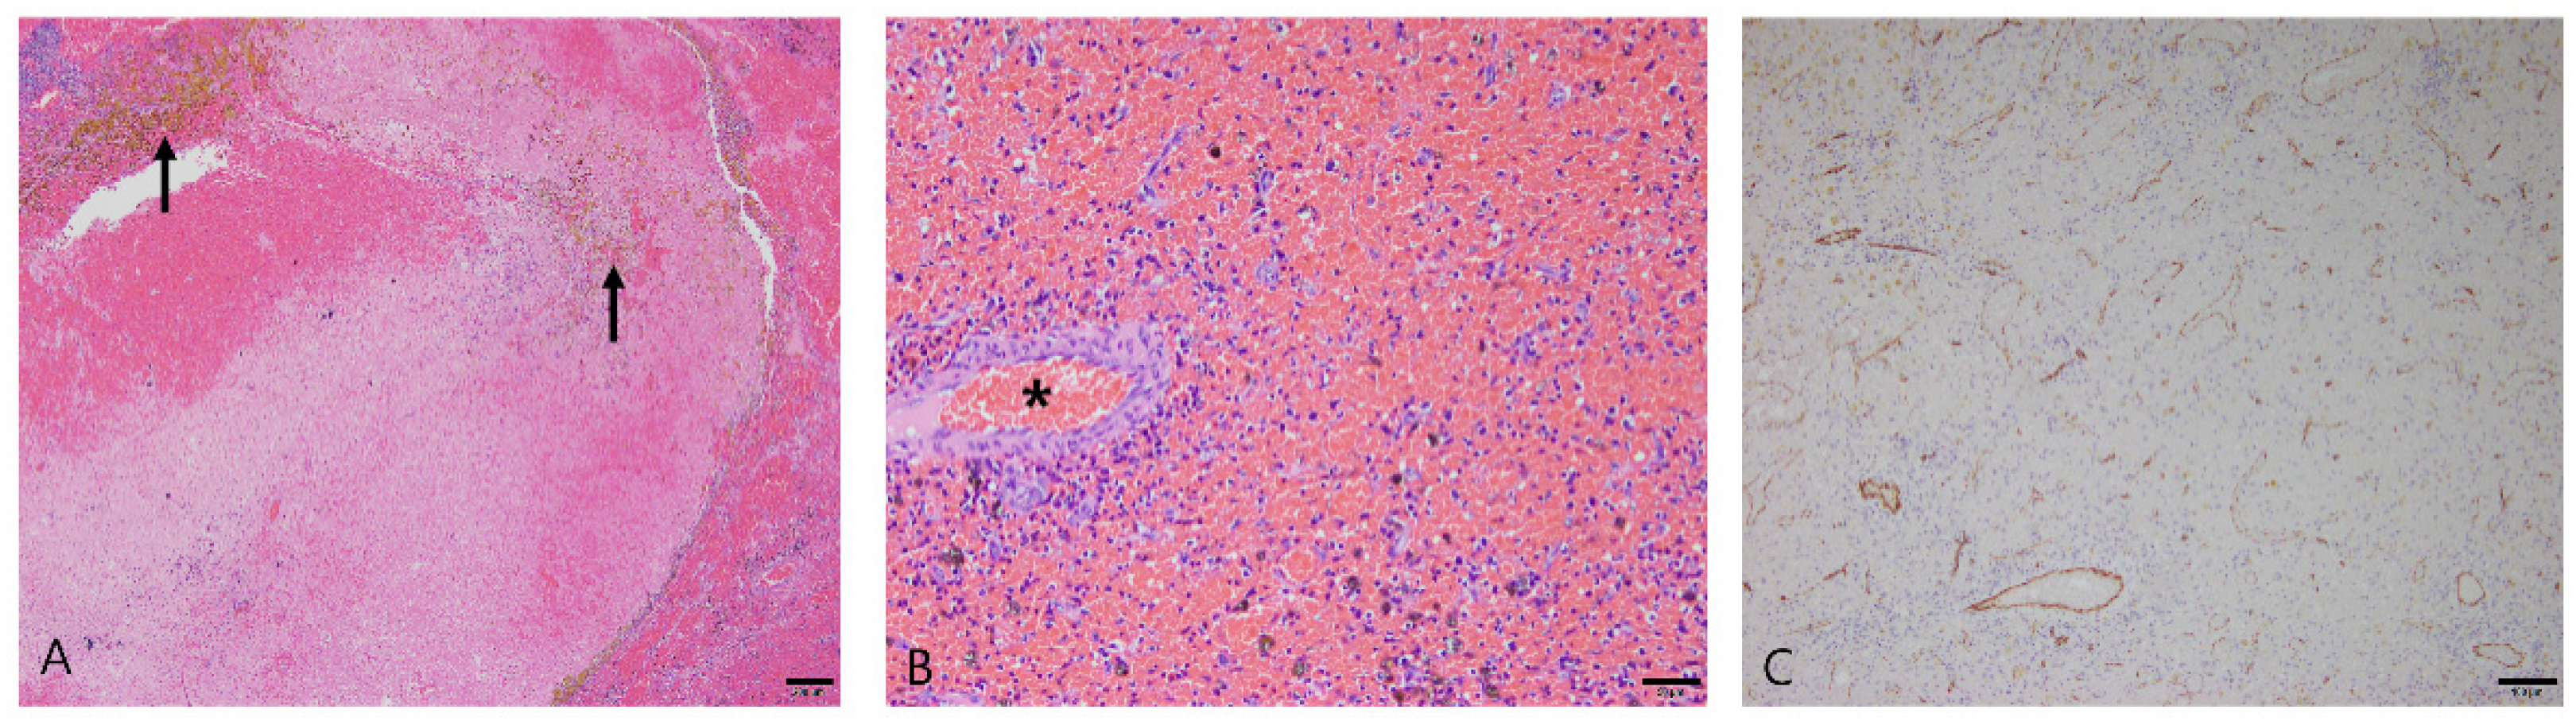

3.2.3. Splenic Hemangiosarcoma

3.2.5. Stromal Sarcomas